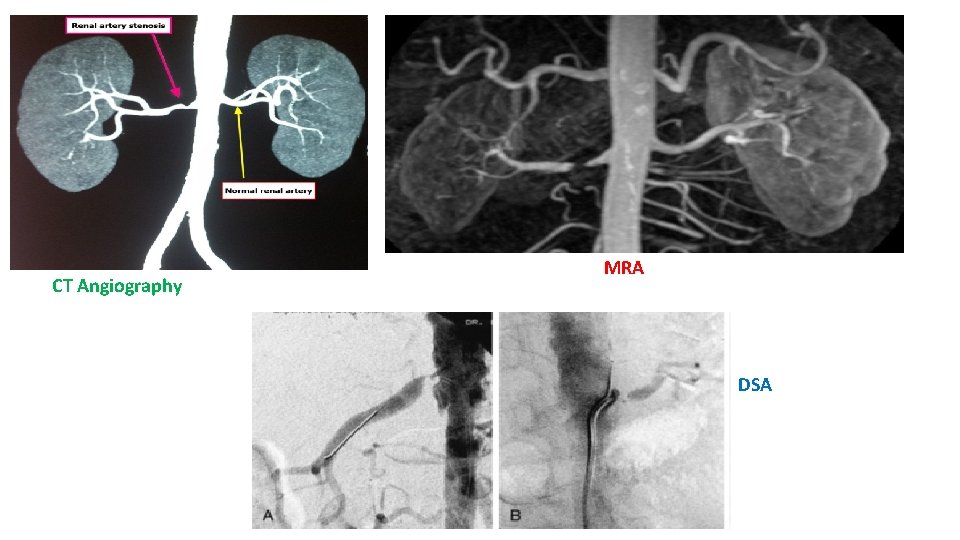

For Renal Artery Stenosis • Isotope scintigraphy (renal scan). • Magnetic resonance angiography. • Duplex Doppler flow studies. • 3 -Dimensional CT. • Arteriography: Digital subtraction angiography (DSA) or classic. • Conformation by : angiography or CT angiography. (fluoroscopic angiography may be needed, especially to detect intrarenal arterial stenosis)

CT Angiography MRA DSA